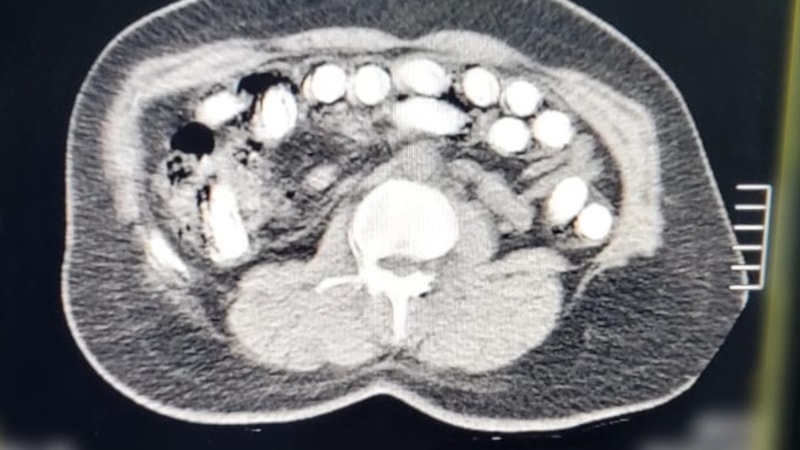

Gözaltına alınan A.G.'nin röntgen ve tomografi görüntülerinde midesinde uyuşturucu bulunduğu belirlendi. Gerçekleştirilen ameliyat sonucunda, şüphelinin midesinden 88 kapsül halinde toplam 974,52 gram afyon sakızı çıkarıldı. A.G., taburcu edildikten sonra her iki şüpheli "uyuşturucu madde ticareti" suçlamasıyla mahkemeye sevk edilerek tutuklandı.